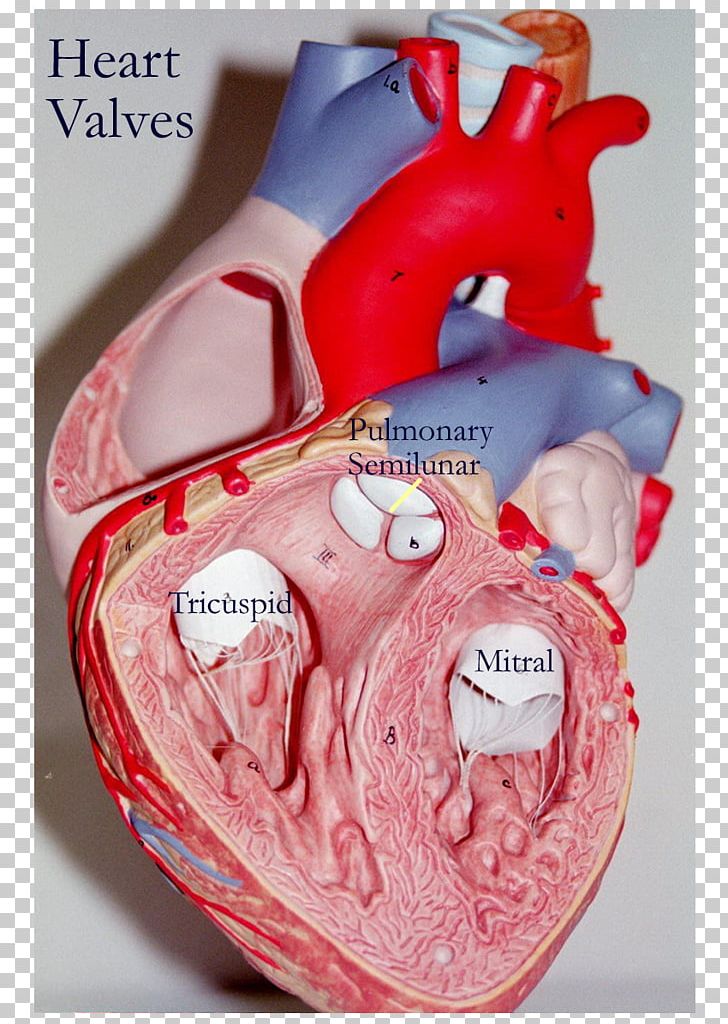

The tricuspid valve consists of three flaps or leaflets however cases are found when the tricuspid valve consists of only two or even four leaflets instead of the traditional three. The tricuspid valve lies within the right trigone.

Tricuspid valve anatomy. An appreciation of the complex and variable anatomy of the tricuspid valve is essential to unraveling the pathophysiology of tricuspid regurgitation. It is the atrioventricular valve that allows blood to flow from the right atrium to the right ventricle. Then blood exits the heart via the pulmonary artery.

Anatomy of the tricuspid valve. The tricuspid valve complex consists of the annulus leaflets right ventricle papillary muscles and chordae tendinae. Right atrioventricular valve tricuspid valve these are large veins that transport deoxygenated blood from the body back to the heart.

The valve has anterior posterior and septal leaflets cusps the bases of which attached around the av orifice to the fibrous ring fibrous skeleton of the heart. Blood collects within the right atrium and it must flow through the tricuspid valve in order to enter the right ventricle. The tricuspid valve functions as a one way valve that closes during ventricular systole to prevent regurgitation of blood from the right ventricle back into the right atrium.

Heart Valve Anatomy Tricuspid Valve Png Clipart Anatomy

Heart Valve Anatomy Tricuspid Valve Png Clipart Anatomy